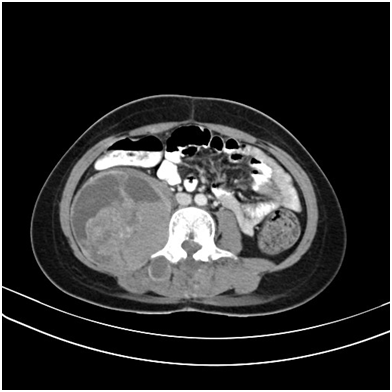

Figure 1 Contrast enhanced axial CT of the abdomen showing a pelvic and iliac fossa mass displacing the displacing the uterus with mesenteric and omental deposits.

Figure 3 Contrast enhanced CT axial sections of the abdomen showing a large heterogeneous mass arising from the pancreatic tail.

Figure 4 T2 weighted coronal sections of the pelvis showing a heterogeneous mass in the scrotum.